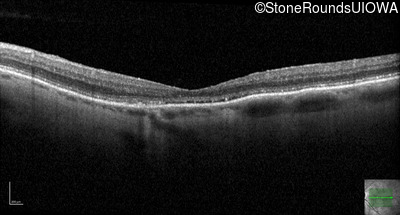

Optical Coherence Tomography - Right - 20/200

Exemplar / OCT Stack

OCT Stack